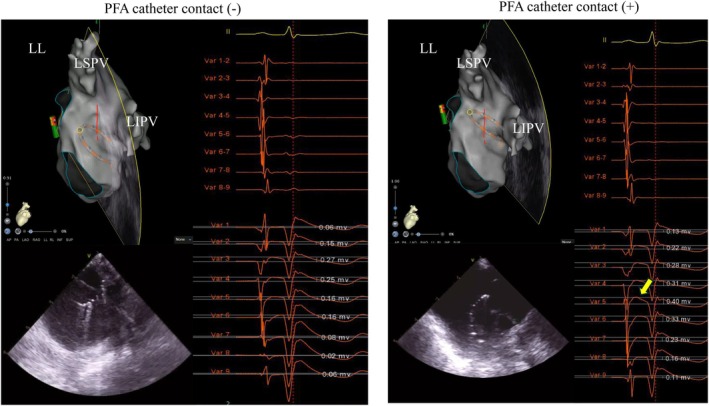

心房P波后的正偏转在单极电图中可作为脉冲场消融过程中导管与组织接触的实用替代标记;与不同解剖区域的有效病变形成相关。

A positive deflection following the atrial P wave in unipolar electrograms serves as a practical surrogate marker for catheter-tissue contact during pulsed field ablation; correlating with effective lesion formation across diverse anatomical regions.